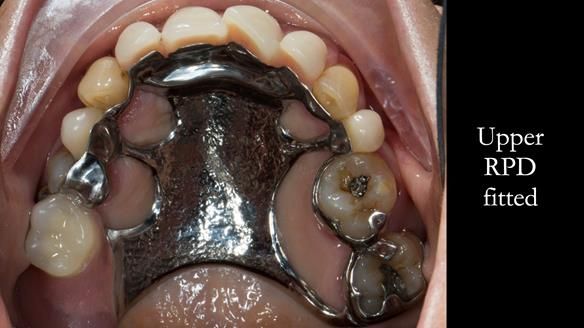

In this edition, I present the removable partial denture treatment for Jean, an 80-year-old woman with a sore mouth caused by a soft tissue-supported 'gum stripper' acrylic denture and a clenching habit. Below, I outline the step-by-step process of her treatment. It wasn't straightforward; I had to remake the denture after it fractured to achieve a satisfactory result. Each patient is unique, and sometimes a new RPD serves as a prototype. Occasionally, I need to make adjustments, learn from any mistakes, and refine the design to get it right.

The treatment has been a success over the past 4 years.